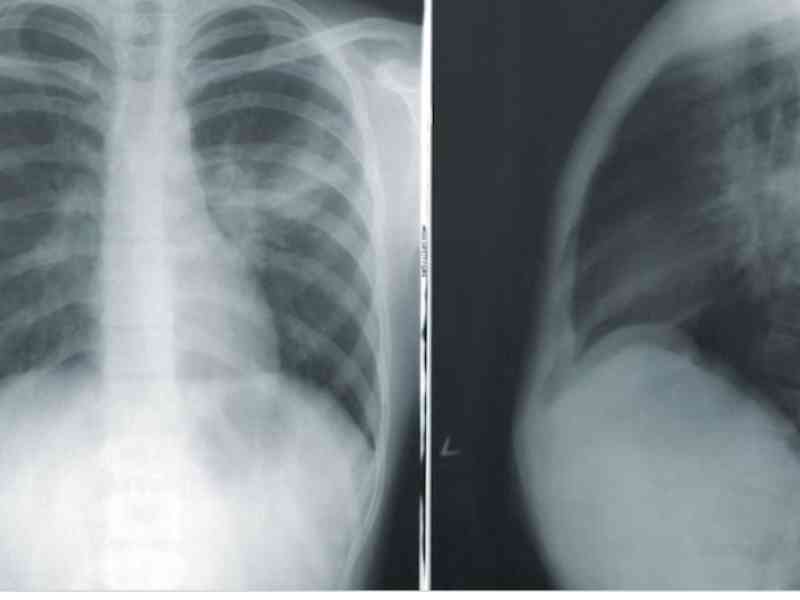

Not a doctor. But this is what I have been asked repeatedly when I was in the hospital for my open heart surgery: “How the heck are you still alive?” Back story: I was basically born with a congenital birth defect which has an extremely high mortality rate. Like 1 in 120,000,000 chance of it happening and about 95% to 99% chance of dying. Not only did I survive it for 20 years, I played lacrosse for four years. Now, the issue was that I was missing a major blood vessel on my heart that is required to pump blood. My body compensated in such an extreme way that the blood vessel on the right side of the heart went down and around the heart and attached itself to aorta.

My heart was basically circulating blood around itself alone and the rest of my body didn’t get enough blood. So how it was found out? Not when I was a baby or kid, no. As an adult, I blew my nose and had a full-on heart attack. Surgeons repeatedly stated and asked “How was I alive” and “You played lacrosse for four years?” Also, the main surgeon stated that anyone with this condition usually dies at birth. They only know of the condition from autopsies.